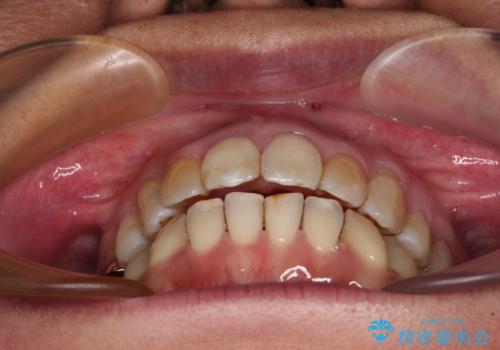

前歯の後戻り インビザラインでの再矯正治療

舌のトレーニングをしっかりと行ってくださり、10ヶ月で希望通りの歯列となりました。

日頃から飲まれる飲み物の影響で着色しやすいため、来院の度に着色除去のクリーニングも行っていました。